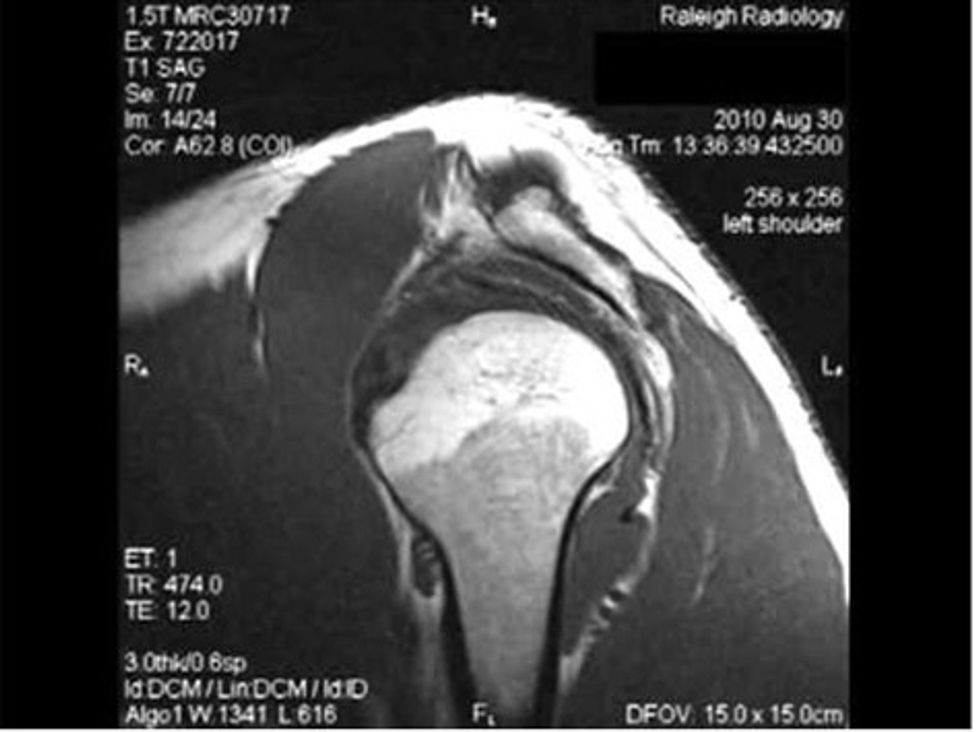

Në MRI pa kontrast në shpatullën e pacientit, një hendek 17-mm është raportuar në futjen e legamentin supraspinatus. Lëngu në hapësirën e përbashkët të nën-deltoid, nën-acromial është raportuar gjithashtu. Këputje e manshetave te ligamenteve dhe legamentin biceps nuk është raportuar në MRI. Edemë e palces se eshtrave ishte e dukshme në tuberozitetin më të madh.

Në fund të 6 muajve të trajtimit, Ultrasonografia e shpatullën tregoi ndryshim në krahasim me kohën para trajtimit. Në MRI pa kontrast mbi shpatullën pacientit, një hendek 14-mm është raportuar në futjen e pjezë supraspinatus.Lëngu në hapësirën e përbashkët të nën-acromial nën-trekëndësh është raportuar. Edema e palces se eshtrave ishte e dukshme në tuberositetin më të madh. Pas përfundimit të programit, pacienti ka iniciuar ngjitje malore dy herë në javë, dhe ai notoi dy herë në javë çdo herë për 2 orë.